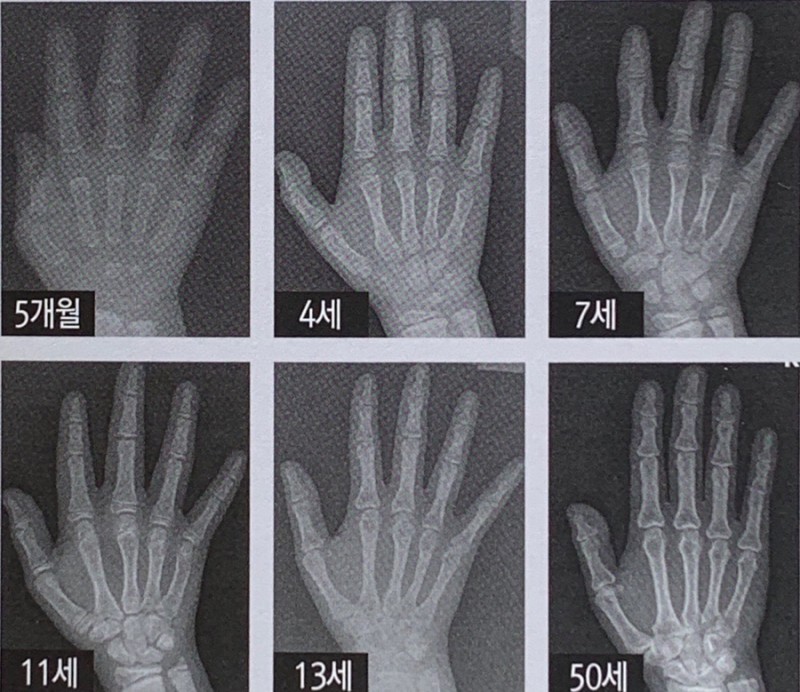

골 연령(뼈나이)도 측정하게 되는데 손 X-ray 검사로 확인 할 수 있으며, 임상 상황을 종합하여

추가로 혈액을 채취하여 호르몬 검사와 염색체 검사를 하게 될 수 있습니다.